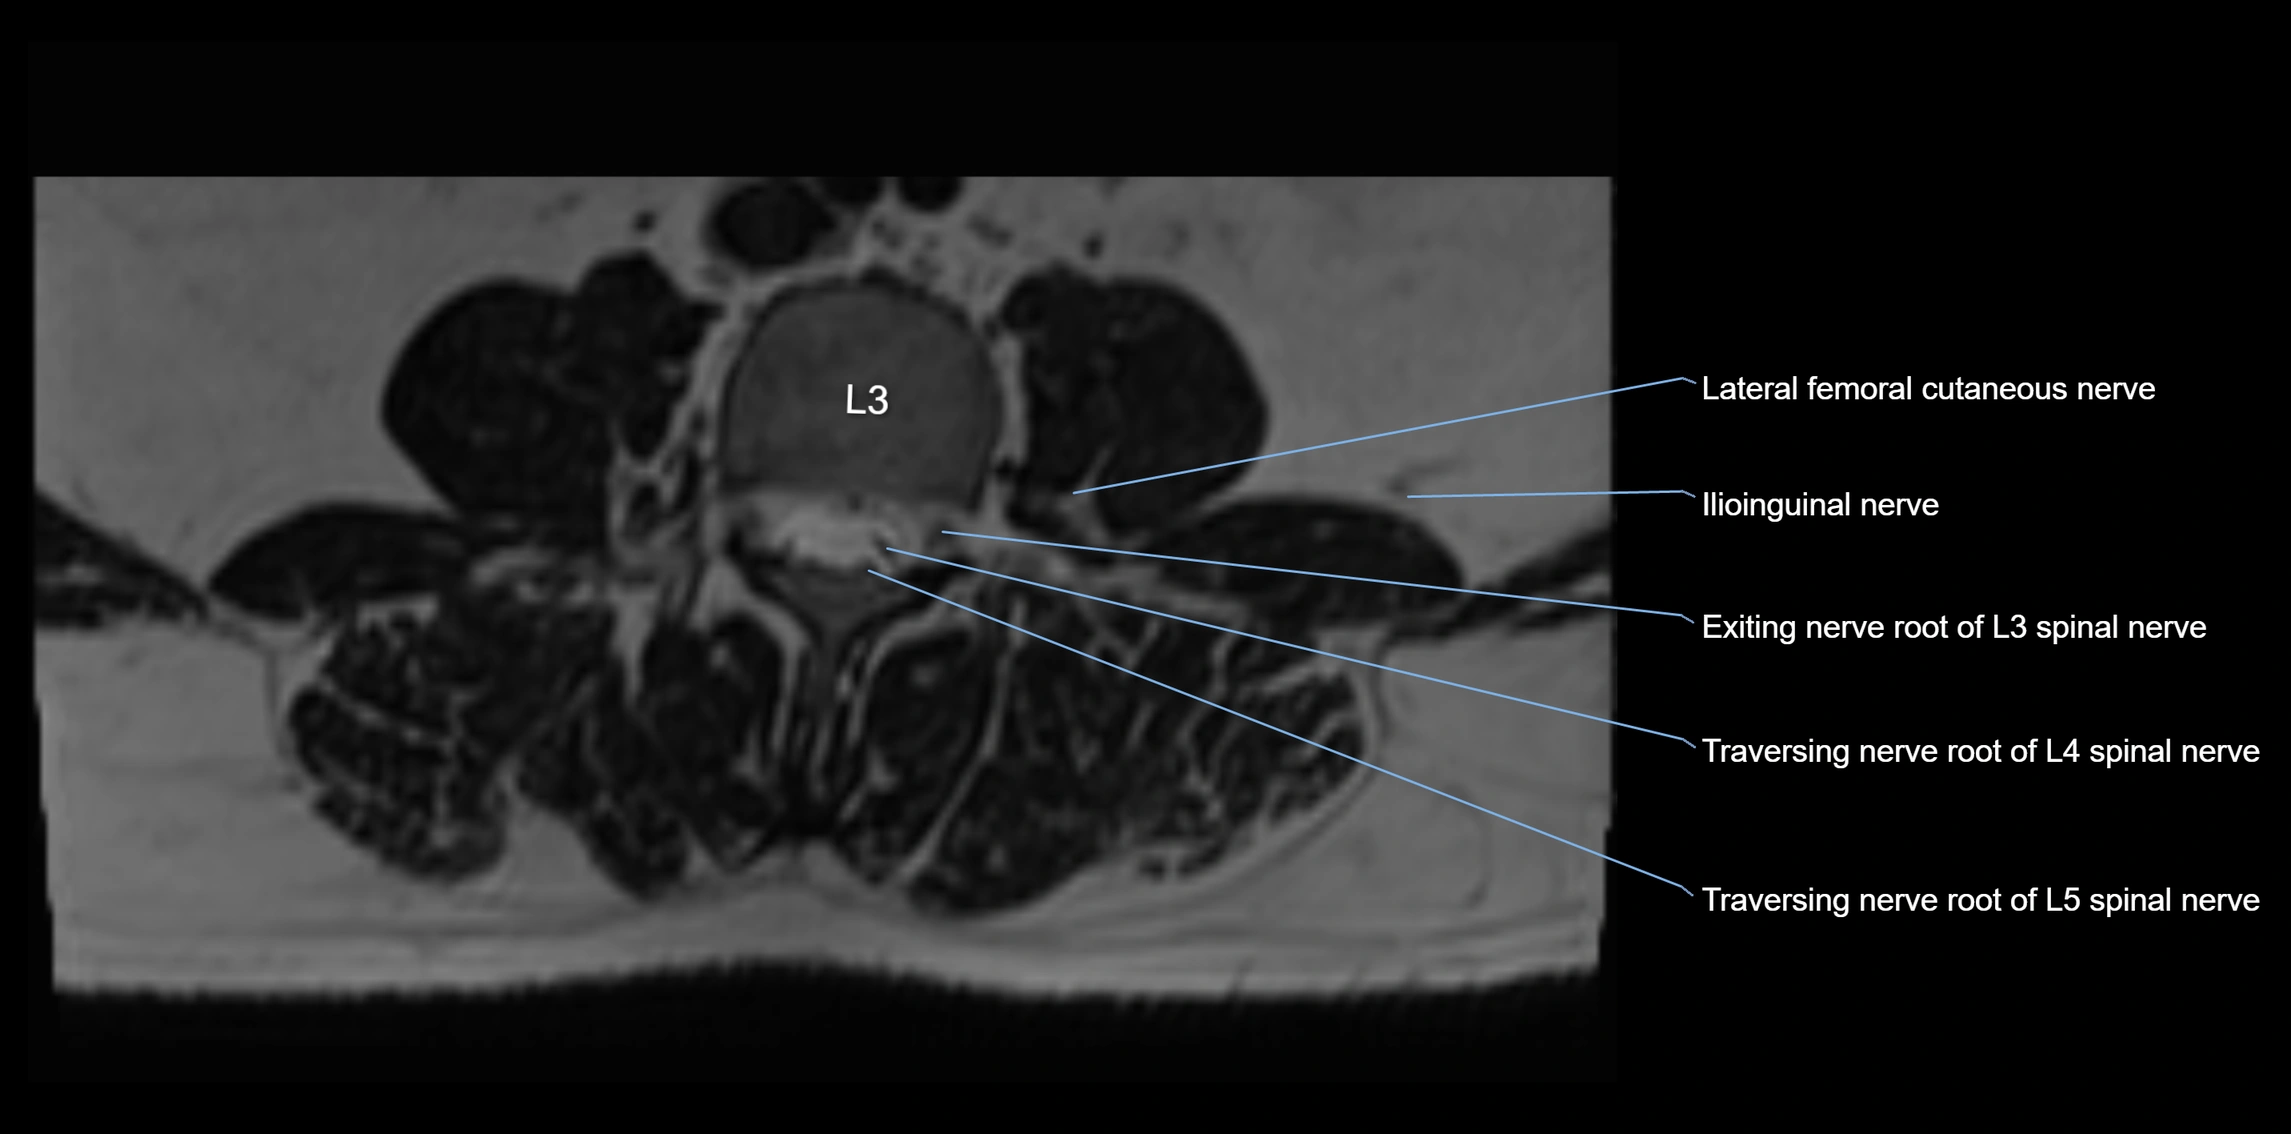

MRI image

image